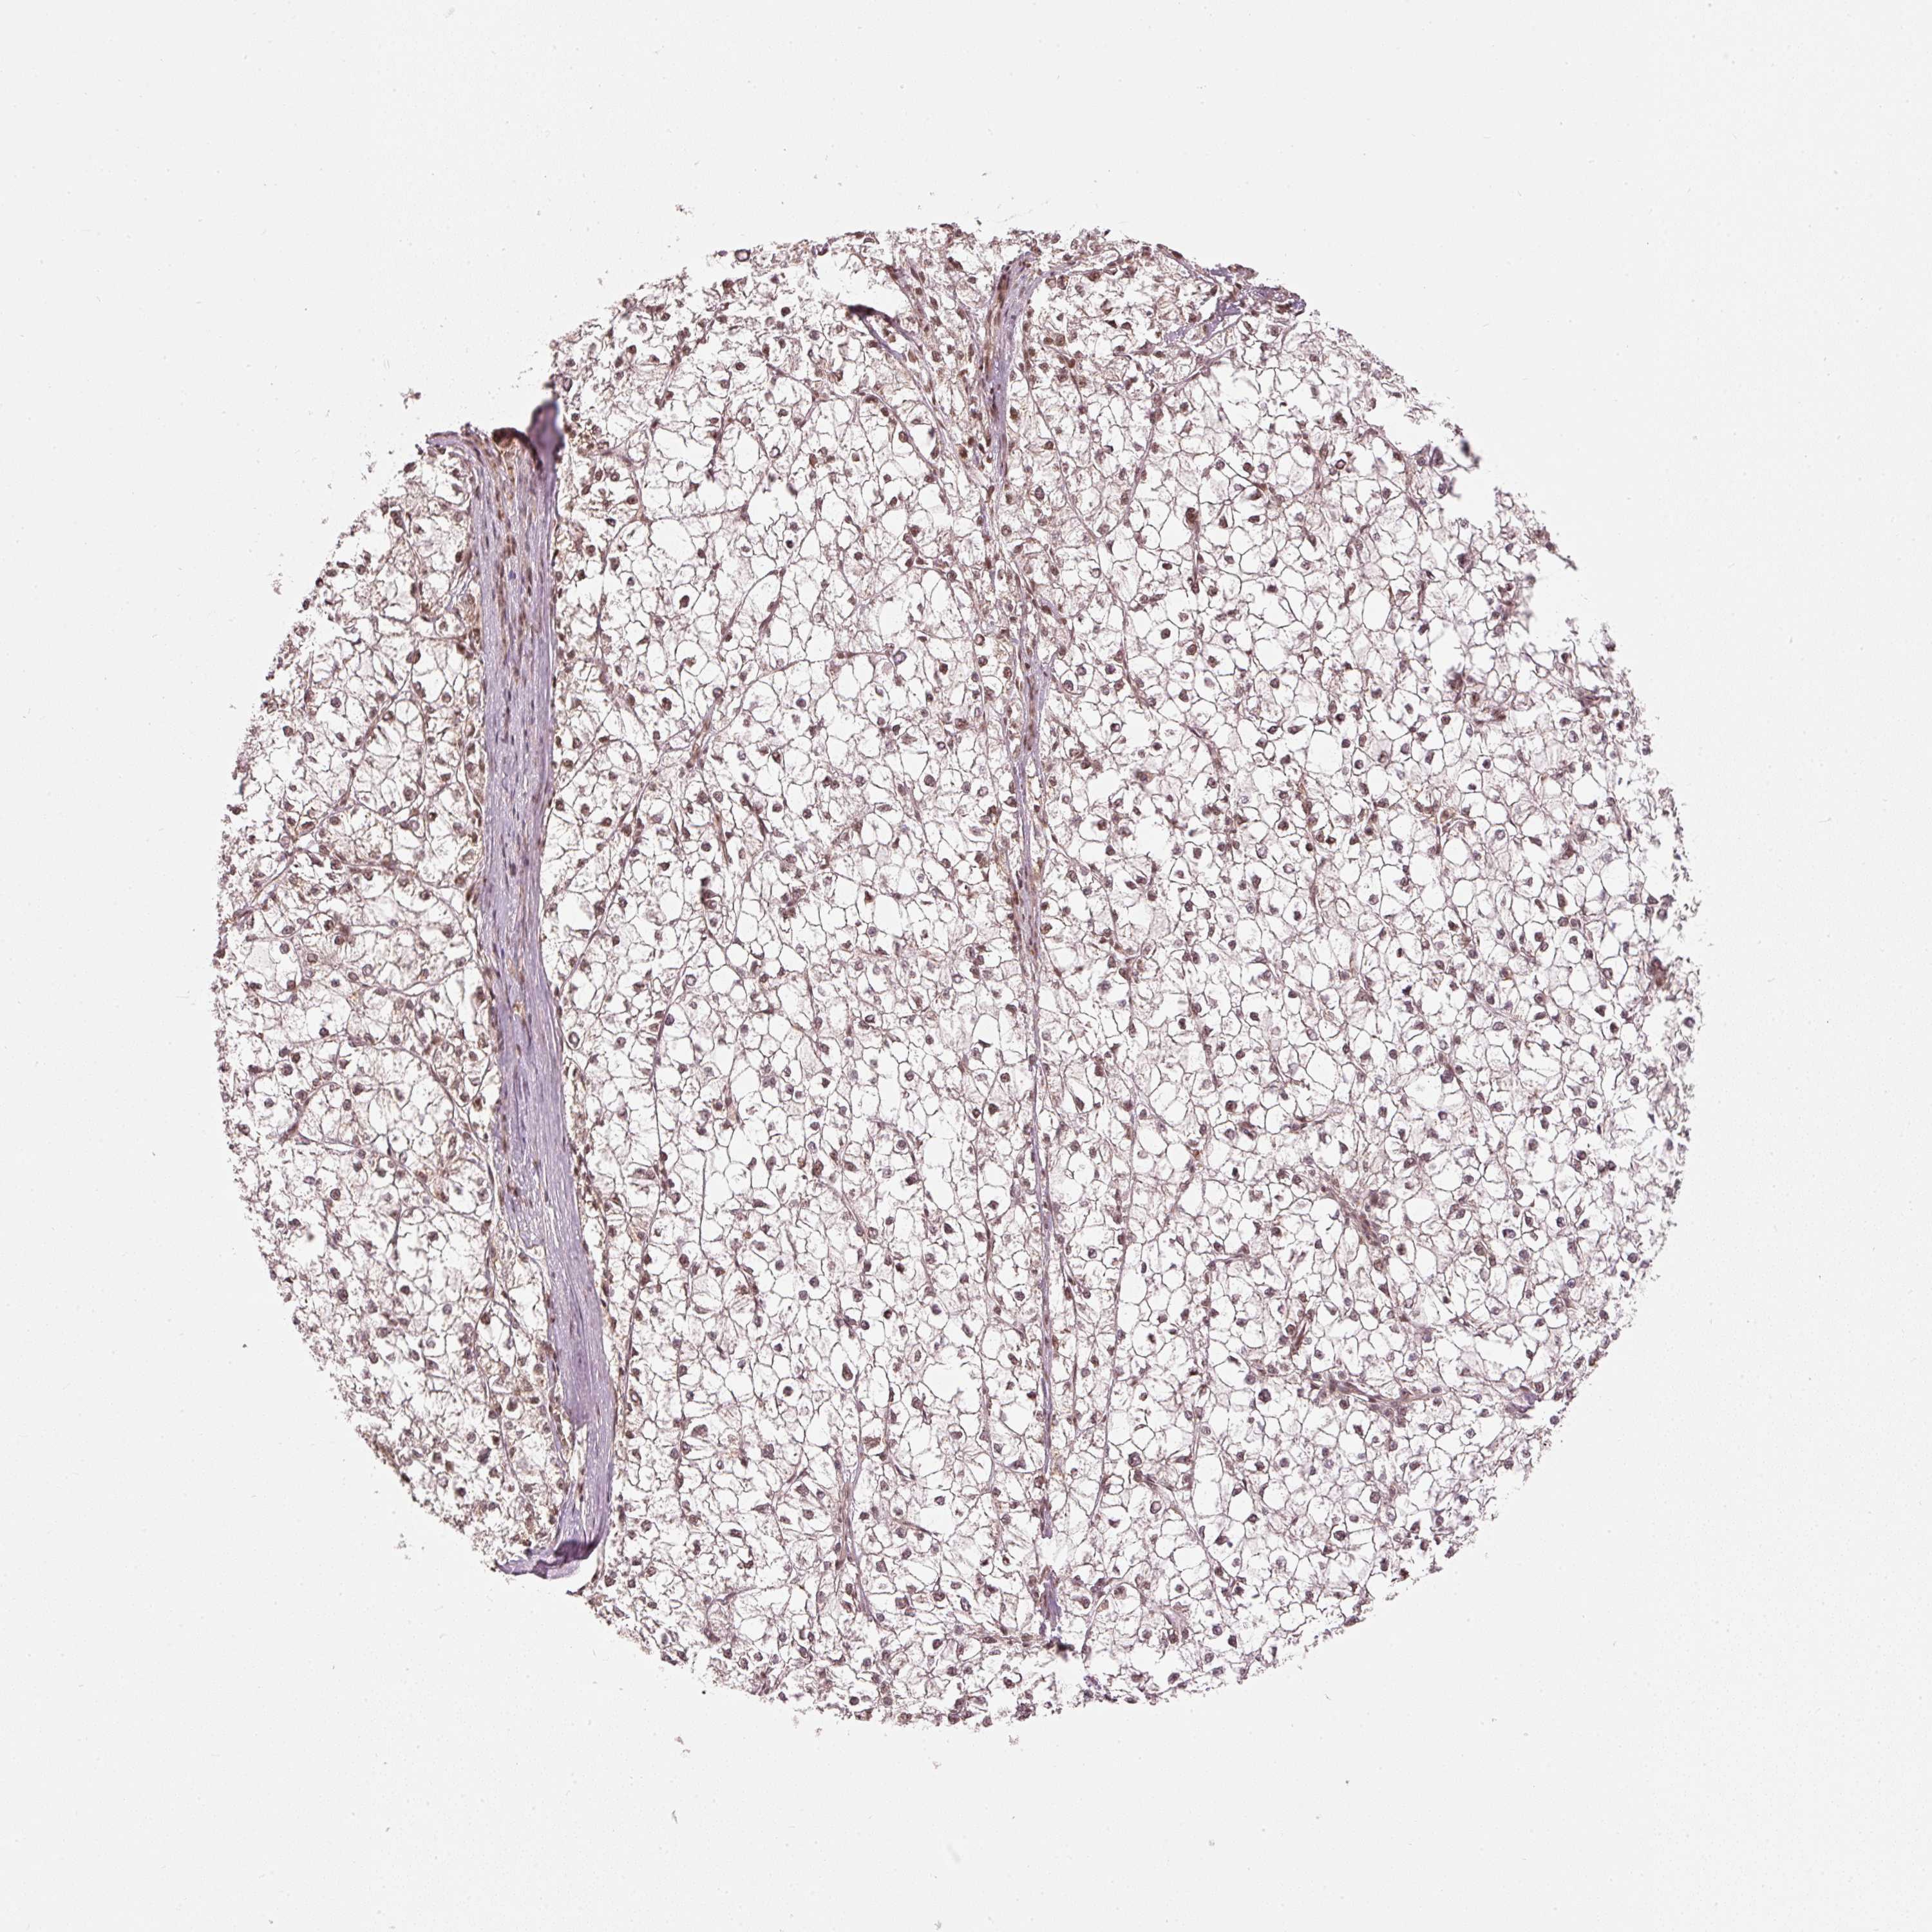

LIVER CANCER - Protein expressioni

A mouse-over function shows sample information and annotation data. Click on an image to view it in a full screen mode. Samples can be filtered based on level of antibody staining by selecting one or several of the following categories: high, medium, low and not detected. The assay and annotation is described here.

Note that samples used for immunohistochemistry by the Human Protein Atlas do not correspond to samples in the TCGA dataset.

Antibody stainingi

Antibody staining in the annotated cell types in the current human tissue is reported as not detected, low, medium, or high, based on conventional immunohistochemistry profiling in selected tissues. This score is based on the combination of the staining intensity and fraction of stained cells.

Each image is clickable and will lead to virtual microscopy that enables deeper exploration of all samples and also displays staining intensity scores, fraction scores and subcellular localization as well as patient and tissue information for each sample.

Antibody HPA052953

Staining

High

Medium

Low

Not detected

Intensity

Strong

Moderate

Weak

Negative

Quantity

>75%

75%-25%

<25%

None

Location

Nuclear

Cytoplasmic/membranous

Cytoplasmic/membranous,nuclear

Carcinoma, Hepatocellular, NOS

Cholangiocarcinoma